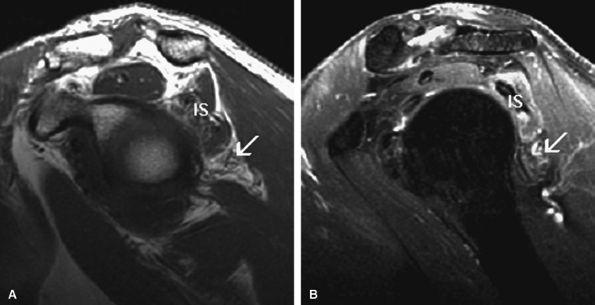

FIGURE 12.6 ● Suprascapular nerve syndrome secondary to a suprascapular varix. Oblique coronal fat-suppressed T2-weighted (A) and axial PD-weighed (B) images demonstrate prominent suprascapular veins (arrow) within the suprascapular incisura and denervation edema of the infraspinatus (IS) muscle.

|

FIGURE 12.7 ● Suprascapular nerve syndrome secondary to a ganglion. Oblique coronal (A) and sagittal (B) fat-suppressed T2-weighted images demonstrate a large cystic lesion occupying the suprascapular incisura and spinoglenoid notch in keeping with a ganglion (arrow). Abnormal T2 hyperintensity consistent with denervation edema involving the infraspinatus muscle (IS) is noted.